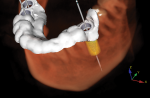

The transfer of the digitally planned implant position to the real position in the mouth via guided surgery is a crucial step in the digital workflow. When the final implant position is planned based on the ideal position, contours, and design of the final restoration, the need for adjunctive procedures such as osseous or soft tissue augmentation can be properly assessed. Benefits of fully guided implant surgery such as shorter procedures, minimal invasiveness, and greatly increased accuracy have been demonstrated throughout the literature.2,6 The surgical guide is 3D-printed and transfers the precise digital planning from the software to the oral cavity (Figure 3). This step is critical to the restorative success of molar implant therapy because the specific position of the dental implant affects posterior emergence profiles, food impaction between restorations and the natural dentition, as well as esthetics.1